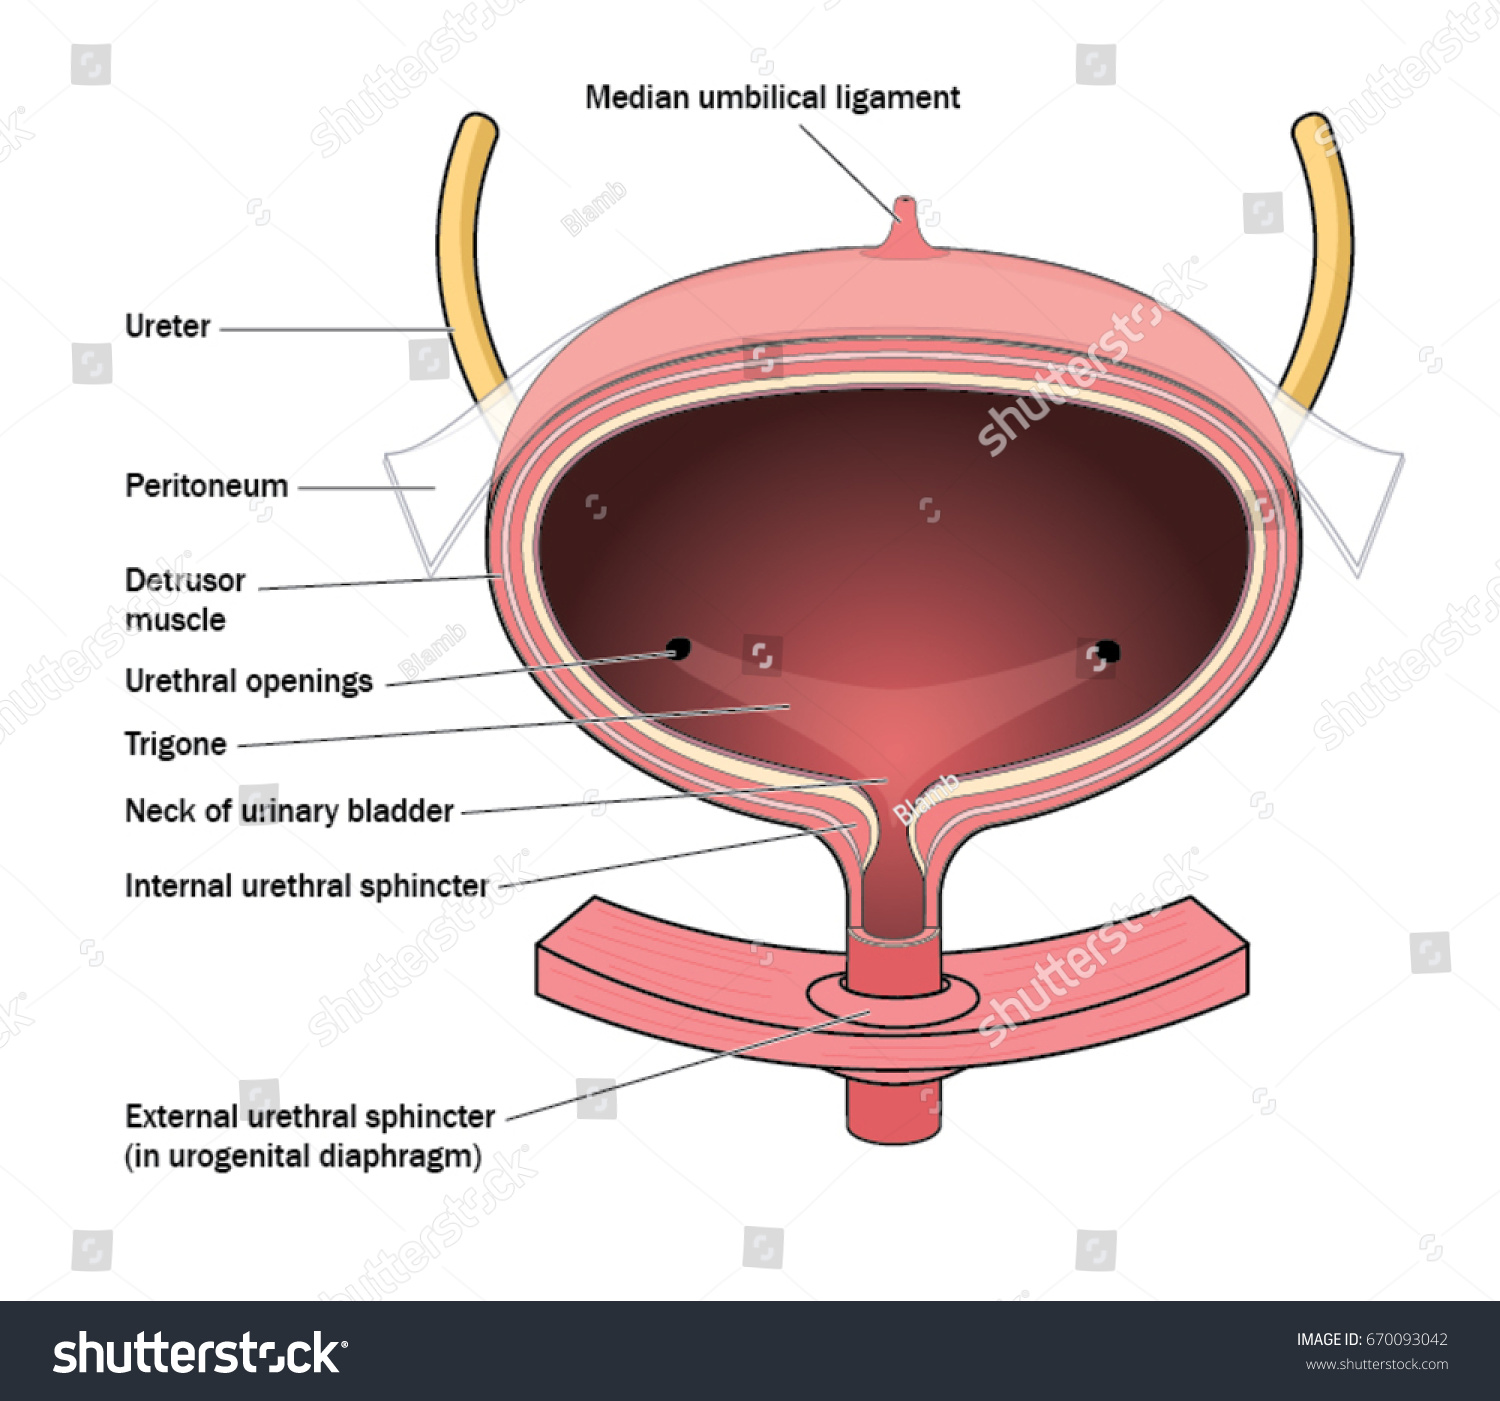

location of the bladder in the human body

Posts: location of the bladder in the human body